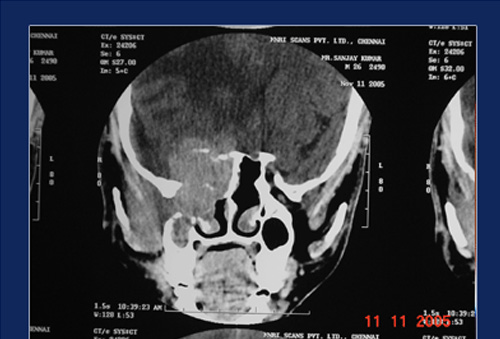

CT scan study of sinuses show typical hyper attentuation inside the sinus cavity called “Metal Dense” shadows. This is due to the fungus trapping heavy metals likes calcium & magnesium. MRI scan show hypointensity of the same areas on T1 – weighted images and signal void on T2 – weighted images.

Expanded sinuses in allergic fungal sinusitis Hyperdense areas suggestive fungal colonies

Fungus shows remarkable ability to expand the sinus walls, so much so the lesions may protrude into the orbit or cranial cavity. Expansion of the ethmoids and frontal sinuses may produce proptosis ( bulging of the eyes). Expansion of sphenoid sinuses may produce loss of vision due to pressure on the optic nerve.